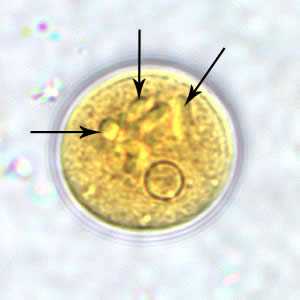

E. polecki cyst in a concentrated wet mount, stained with iodine.

Figure A: Cyst of E. polecki in a wet mount, stained with iodine. Notice the numerous chromatoid bodies (arrows).